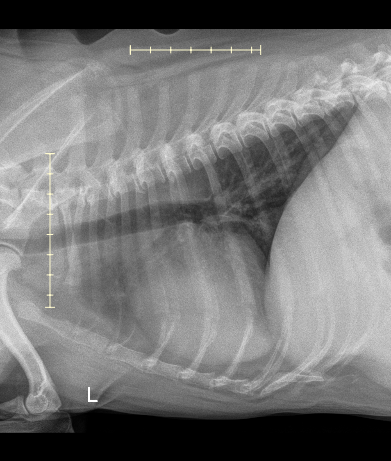

After checking in Gavin and I took a stroll outside, and were called in a few moments later. He and I were taken to a nearby exam room by a technician, and greeted by an oncology team member. After an initial intake and questionnaire, their team took Gavin in the back for a quick check of his mouth, leaving me and my thoughts alone in the room… After ten minutes, their team comes back noting that they’re 99% positive the growth is cancer, possibly melanoma, and that such may have already spread from his mouth to orbital bone / eye socket, and that it may be present in his lungs. At this point my only goal is to obtain information; happy to pay whatever cost for the sedation, needle biopsy, and radiology recommendations.

I leave Gavin in their carefully trained hands. Two hours later I receive a call from their reception team gleefully saying Gavin is awake, and that I may come back to pick him up and chat with the team to discuss their findings. Long story short - cancer is a fibrosarcoma, lungs are clear, and that they expect Gavin to live another three to six months depending on how the tumor continues to grow.